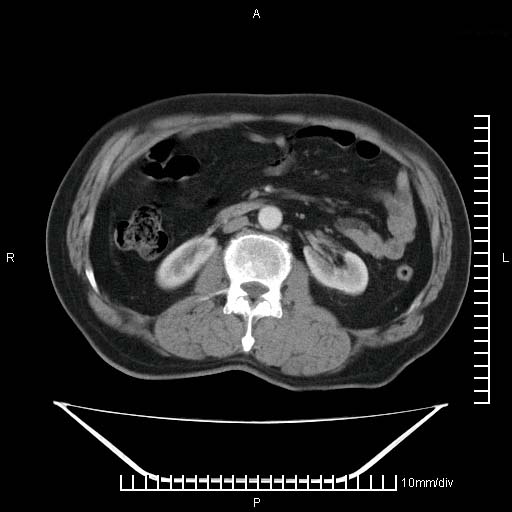

标题: CT25082:肝脏增强:男性,70岁 [打印本页]

标题: CT25082:肝脏增强:男性,70岁

患者以心脏疾病收住院,腹部无明显症状,b超查肝脏有占位。

增强效果不理想。考虑转移,胆囊壁明显增厚,不排除胆囊癌肝转移。

病灶无强化,考虑囊肿。

牛眼征,中心坏死无强化,外缘强化,最外缘又见低密度,考虑转移,与脓肿鉴别

肝内多发转移瘤,右下肺炎症并少量胸水。胃壁增厚建议胃镜,胰尾部“病变”为肠管。

1)肝脏多发性转移瘤(不排除胰尾癌转移所致可能)。2)腹水。3)右侧少量胸腔积液。

ct25082 结果:转移瘤

外院mr结果:胰尾恶性占位。